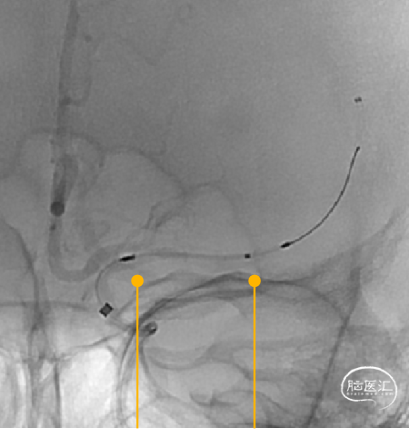

1、左侧颈内动脉造影

2、Synchro微导丝过病变

微导丝过病变

调整微导丝选择较粗、较平直的分支动脉。

SL-10微导管造影

3、Gateway球囊扩张

4、Neuroform® EZ定位释放

沿微导丝送入XT-27微导管,经微导管送入3.5mm*15mm Neuroform® EZ至狭窄处,定位后释放。

示意图

注意支架头端及尾端位置

Neuroform® EZ释放过程